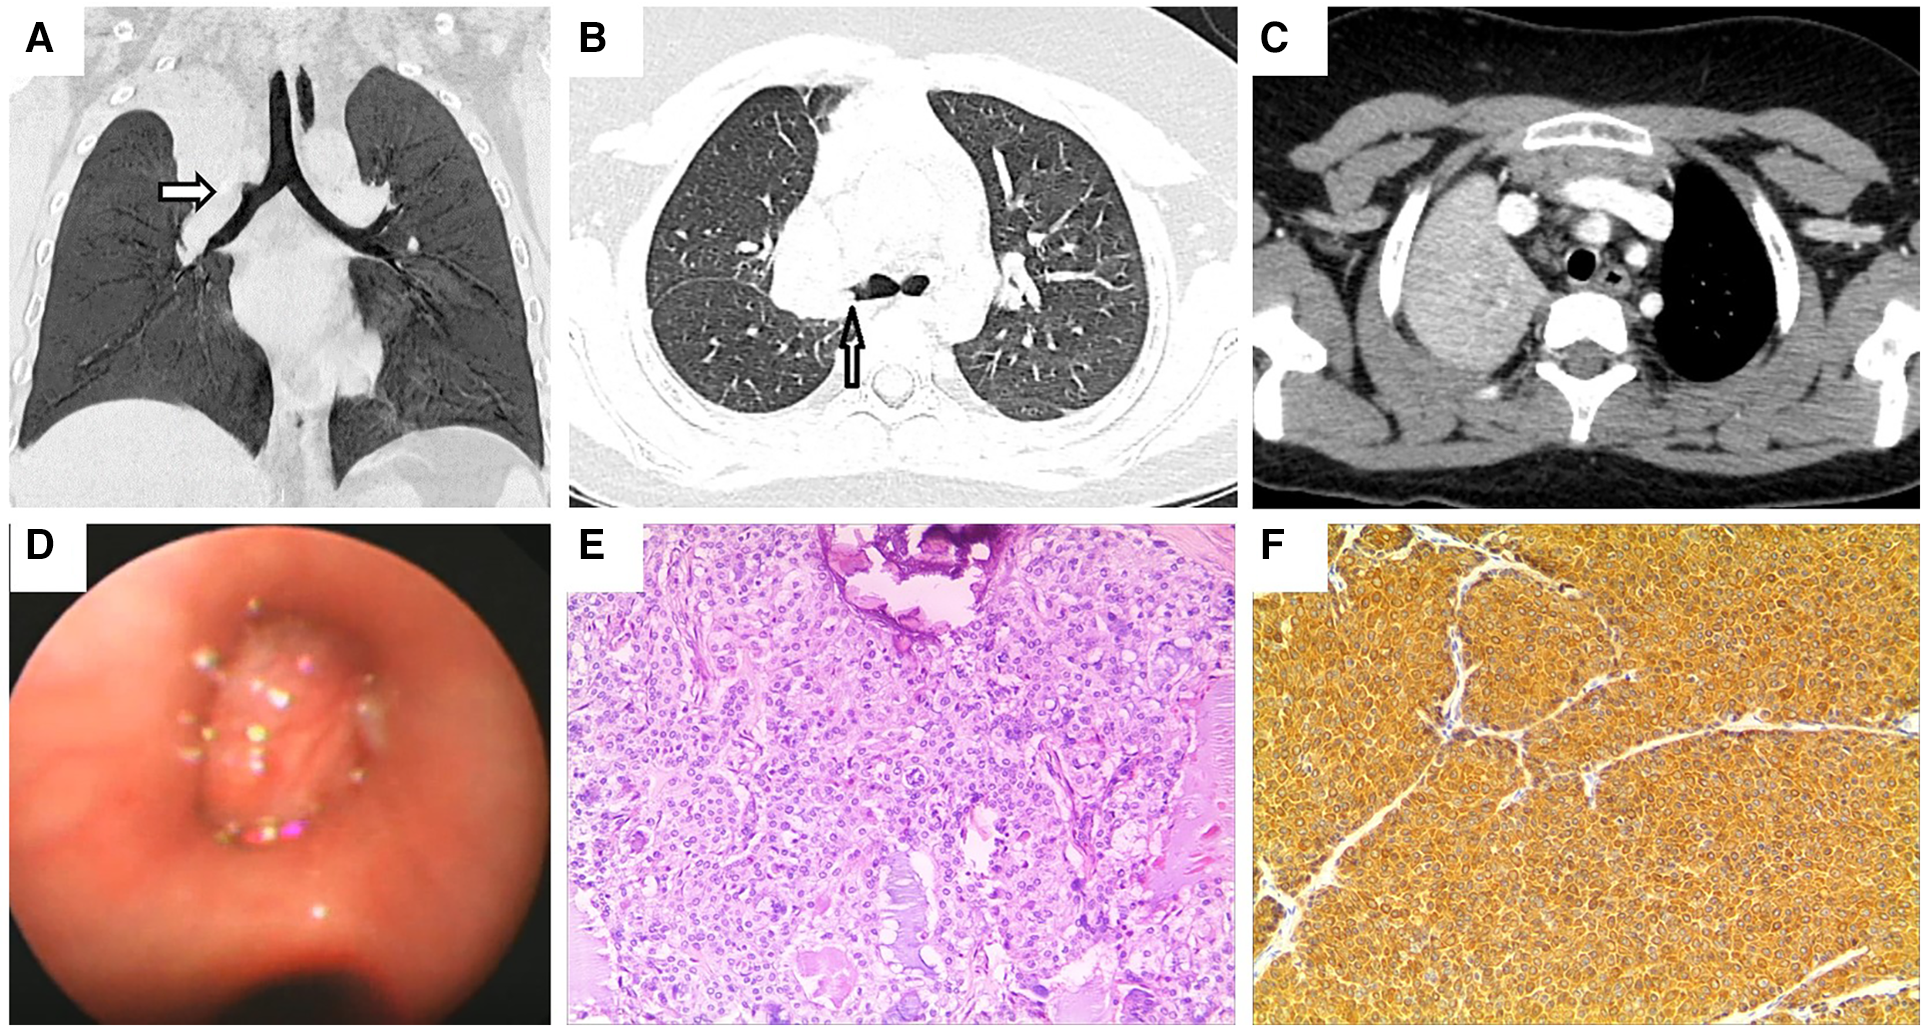

A previously healthy 9-year-old girl was admitted to the hospital with persistent cough and chest pain for over 10 days. Remarkably, she showed no current fever, hemoptysis, nausea, abdominal pain, vomiting, diarrhea, chest pain, palpitations, or weight loss. Moreover, her medical history was devoid of any surgeries, traumas, encounters with sick individuals, aspiration episodes, or exposure to infectious and/or hazardous substances. Furthermore, she had no family history of asthma, diabetes, immunodeficiency, malignancy, or tuberculosis. The patient had encountered a bout of upper right pneumonia more than a year before the current presentation. However, after the patient's respiratory symptoms improved, the chest radiograph was not reviewed, and no further tests were performed. On the fifth day of experiencing chest pain, the patient visited a local hospital. Subsequent chest CT showed atelectasis of the upper lobe of the right lung, and flexible bronchoscopy was recommended. Her parents referred her to our facility for further evaluation and management. Blood routine and biochemical tests were all within normal ranges, and the T-spot test, oncological biomarkers, and purified protein derivative (PPD) test yielded negative outcomes. Chest contrast-enhanced CT revealed a space-occupying lesion at the bronchial opening of the right upper lobe, with uneven enhancement (Figures 1AC). On the fifth day of hospitalization, flexible bronchoscopy (Figure 1D) and biopsy were performed. However, owing to the challenges linked with performing a biopsy in the right upper lobe, only a few specimens could be obtained. Due to unsatisfactory biopsy results, a multidisciplinary consultation was conducted, and a right superior lobectomy was recommended due to the high possibility of a bronchial tumor being the underlying condition. Eventually, a right upper lobectomy was performed. The lesion was a firm mass with a faint yellow surface. Hematoxylin and eosin (HE) staining of the specimen showed that the tumor cells were arranged in nests or glandular tubes, with abundant cytoplasm and epithelioid appearance, and the area was rich in mucus (Figure 1E). Histopathological examination revealed a PMEC with tumor-free surgical margins and metastasis to the mediastinal lymph node. Immunohistochemical analysis yielded remarkably positive results for the expression of cytokeratin (CK), CK-7, CK-19, and periodic acid-schiff stain (Figure 1F), while showing relatively weaker positivity for epithelial membrane antigen (EMA). Synaptophysin expression was notably absent. No recurrence was observed during the 3-month postoperative follow-up.

FIGURE 1

www.frontiersin.org

Figure 1. Chest enhanced CT, bronchoscopy, pathological image, and immunohistochemistry assay of case 1. (A,B) Contrast-enhanced CT images of the chest show a space-occupying lesion at the right upper lobe bronchial opening. Arrows indicate space-occupying lesions. (C) Arrow indicates right upper lobe atelectasis. (D) Visual depiction of flexible bronchoscopy, confirming the presence of a ball-shaped soft solid tumor originating from the right upper lobe bronchus. (E) Photomicrograph (HE × 100) shows the confirmed diagnosis of pulmonary mucoepidermoid carcinoma. (F) Photomicrograph shows positive immunohistochemical staining for CK (magnification × 100).